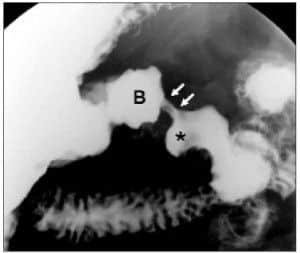

•  ULCERA DUODENAL

• ESTENOSIS DISTAL AL BULBO Y NICHO ULCEROSO